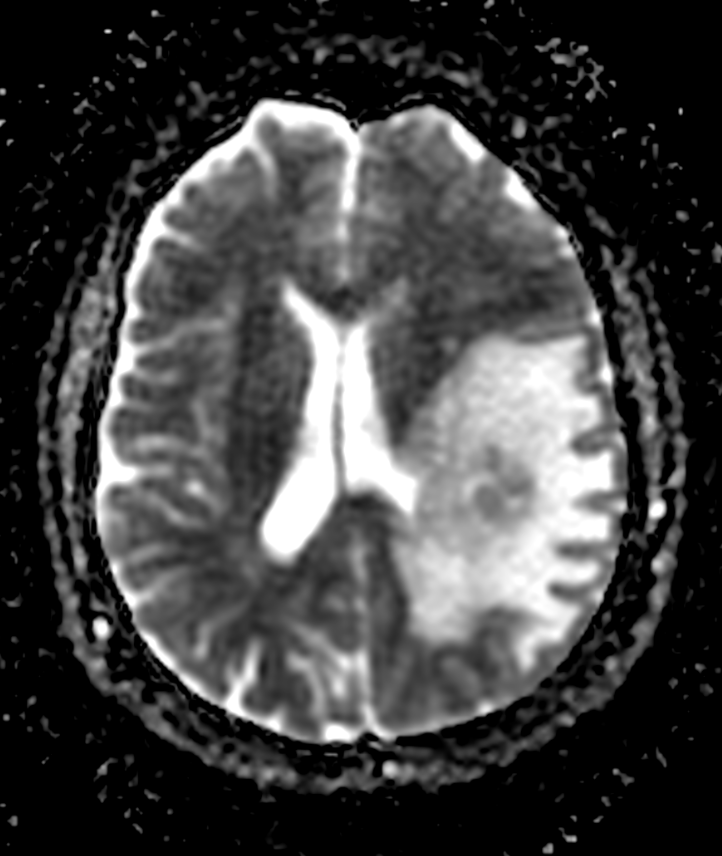

Mapa ADC (RM difusión)